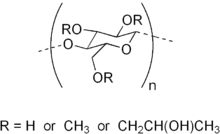

Hypromellose (INN), short for hydroxypropyl methylcellulose (HPMC), is a semisynthetic, inert, viscoelastic polymer used in eye drops, as well as an excipient and controlled-delivery component in oral medicaments, found in a variety of commercial products.[1][2]

Hypromellose is a solid, and is a slightly off-white to beige powder in appearance and may be formed into granules. The compound forms colloids when dissolved in water. This non-toxic ingredient is combustible and can react vigorously with oxidizing agents.[4]

Hypromellose in an aqueous solution, like methylcellulose, exhibits a thermal gelation property. That is, when the solution heats up to a critical temperature, the solution congeals into a non-flowable but semi-flexible mass. Typically, this critical (congealing) temperature is inversely related to both the solution concentration of HPMC and the concentration of the methoxy group within the HPMC molecule (which in turn depends on both the degree of substitution of the methoxy group and the molar substitution). That is, the higher the concentration of the methoxy group, the lower the critical temperature. The inflexibility/viscosity of the resulting mass, however, is directly related to the concentration of the methoxy group (the higher the concentration is, the more viscous or less flexible the resulting mass is).

Degree of substitution is the average level of methoxy substitution on the cellulose chain. Since there are maximum three possible sites of substitution with each cellulose molecule, this average value is a real number between 0 and 3. However, degree of substitution is often expressed in percentages.

Molar substitution

Molar substitution is the average level of hydroxypropoxy substitution on the cellulose chain. Since hydroxypropoxy base can be attached to each other on side chains and does not each require a base substitution site on the cellulose molecule, this number can be higher than 3. However, molar substitution is also often expressed in percentages.